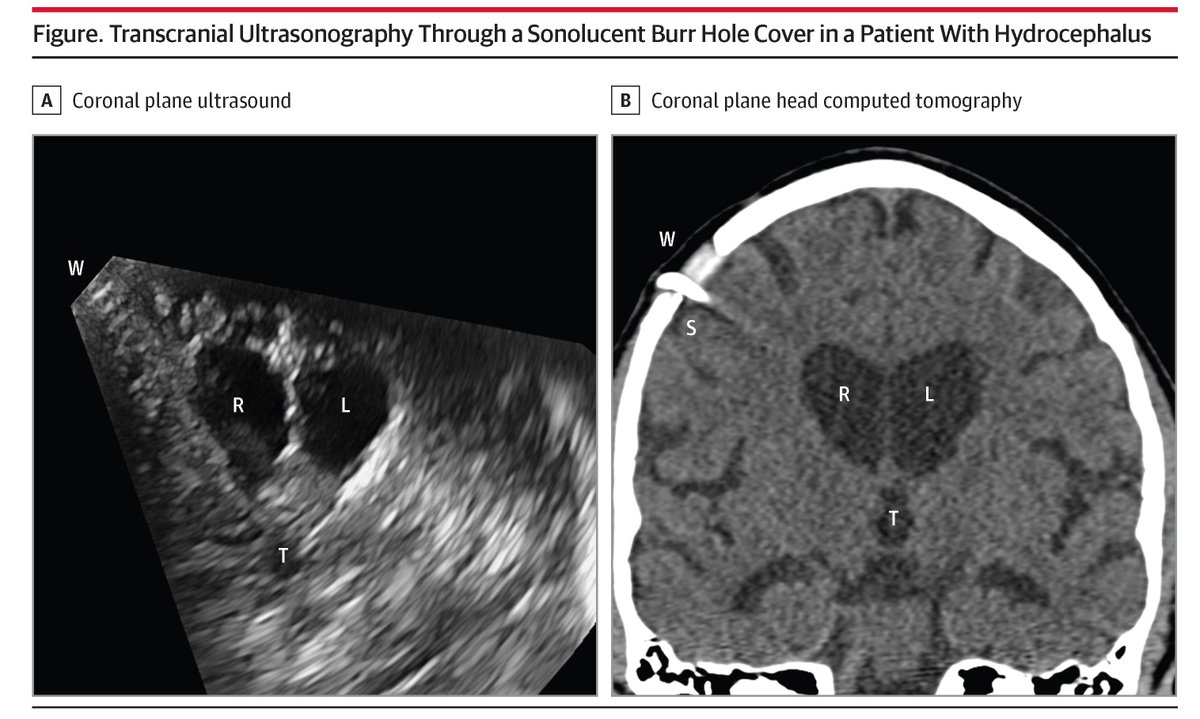

Grateful to work with Dr. Ryan Lee and Dr. Mark Luciano on novel cranioplasty technologies! @HopkinsNsurg @HopkinsMedicine @HopkinsEngineer

@JAMASurgery

Sonolucent cranioplasty revolutionizes neurosurgery by facilitating bedside ultrasound assessments, reducing CT/MRI use, enhancing patient safety, and lowering costs. https://t.co/RP5o2jg4LM